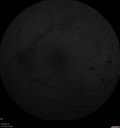

20 year old mane with fresh vitreous hemorrhage in the right eye. At age 15 he had a PPV and laser in the left eye and laser in the right eye. The vision is OD 20/80 PH 20/25, OS 20/25. The left eye has a mild cataract. He had prior testing for coagulopathies which was negative. Testing done for syphillis and TB was negative. Additional laser was done to prevent further bleeding in the right eye.